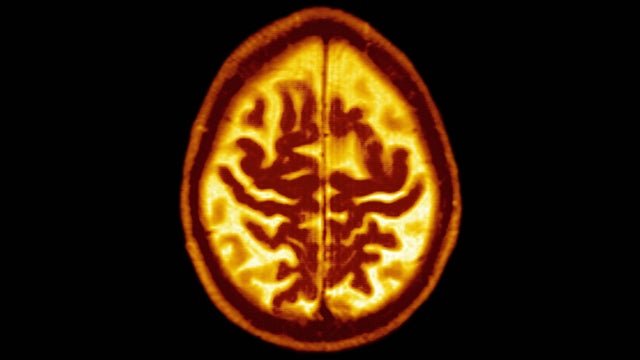

A simple blood test could predict if a patient will develop Alzheimer's disease up to 16 years before symptoms begin, a new study finds.